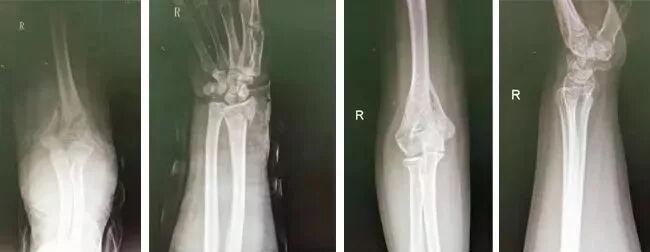

病例五

橈骨遠端骨折

患者劉某,男,8歲,因摔倒后手腕撐地導(dǎo)致左側(cè)橈骨遠端骨折,患者年齡較小,家屬希望予以保守治療,來到嘉興邦爾骨科醫(yī)院富陽骨傷就診后,進行手法整復(fù)、固定,當(dāng)即復(fù)位成功,后予以外敷張氏金黃散。

經(jīng)過每周換幫,1個月后骨折愈合,1個半月功能恢復(fù)。

手法整復(fù)前后對比圖